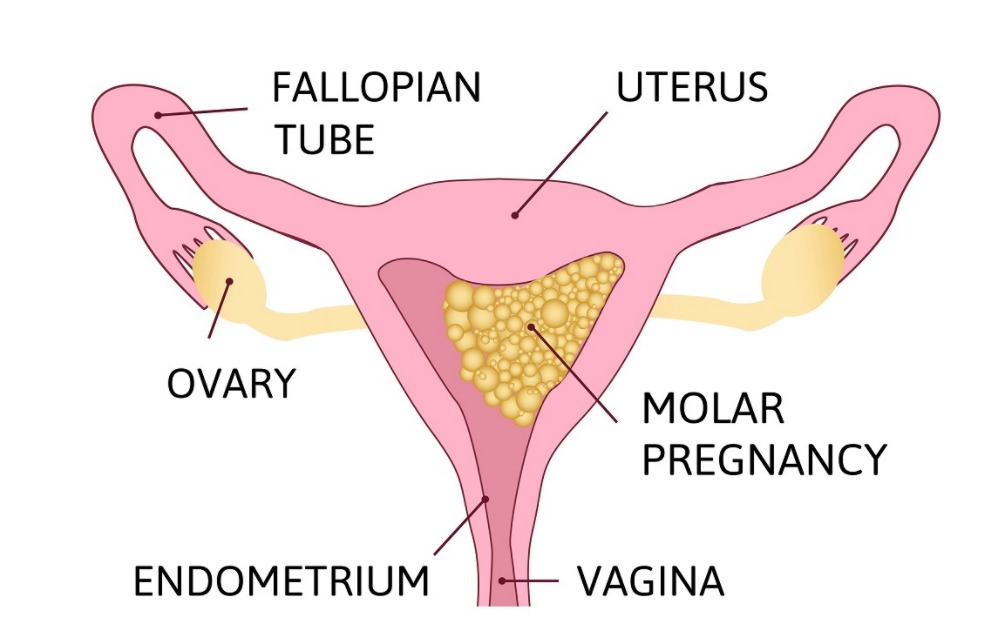

Kehamilan Anggur Ohcantik Com

Kehamilan Anggur Ohcantik Com

Kehamilan Anggur Ohcantik Com

Kehamilan Anggur Ohcantik Com

Kehamilan Anggur Molar Pregnancy Sejenis Noncancerous Tumor Ohcantik Com

Kehamilan Anggur Molar Pregnancy Sejenis Noncancerous Tumor Ohcantik Com